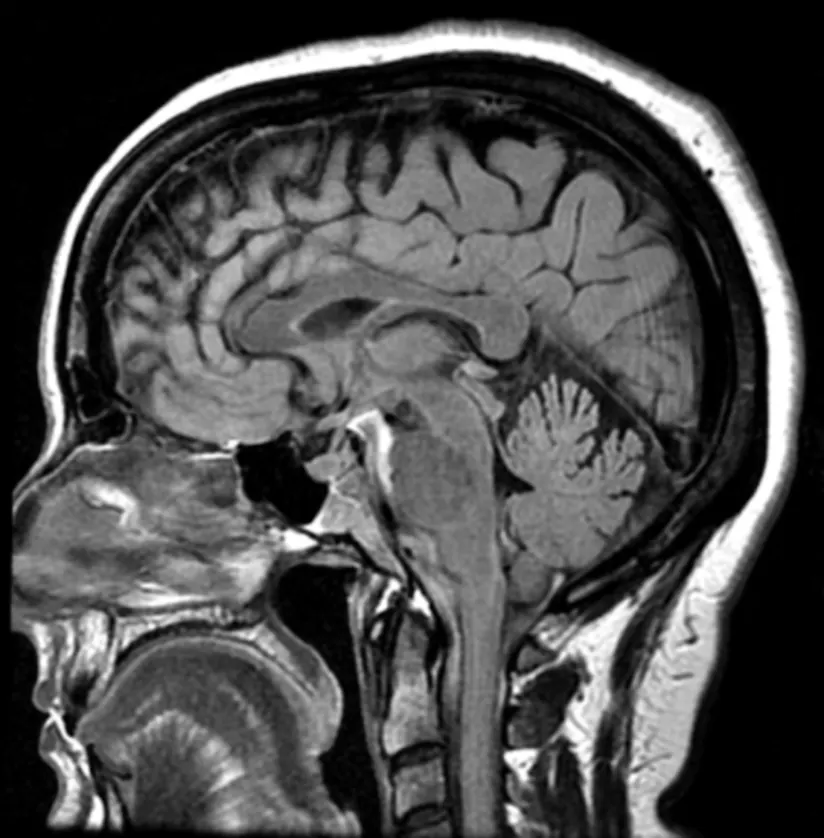

磁共振成像(MRI) - 放射学的特定技术,以创建体内内部部位的非常详细的图像 - 是诊断和监测多发性硬化症(MS)的重要工具。曾经诊断出来,有MS的人通常会接受年度MRI扫描。有些人可能更频繁的扫描,一些越来越频繁。

MRI扫描仪使用强磁场来生成图像。MS中的标准成像协议建议使用至少3个TESLA(3T)“封闭机”以获得最佳效果。成像序列专注于静脉施用造影剂,钆,钆,增强某些解剖学特征前后脑和/或脊髓的白质和/或脊髓。